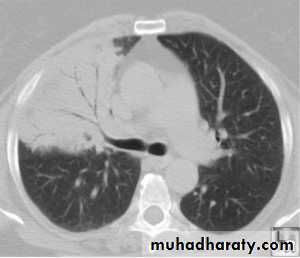

Chest radiograph may show reticulonodular or interstitial infiltration, primarily in the lower lobes.

Young to middle-aged, large-scale epidemics, or sporadic, often mild, self-limiting disease. Headaches and a longer duration of symptoms before hospital admission.The pneumonia resembles that of Mycoplasma pneumonia in that patients often have prominent antecedent upper respiratory tract symptoms, fever, nonproductive cough, mild to moderate illness, minimal findings on chest auscultation, and small segmental infiltrates on chest x-ray.

These are small, gram-negative, obligate intracellular bacteria.Chest x-ray is nonspecific and may show pneumonic lesions that are usually patchy in appearance. but can be hazy, diffuse, homogeneous, lobar, wedge-shaped, nodular, or miliary.

Legionnaires' disease ; No diagnostic features on the chest X-ray distinguish it from other pneumonia. But may showing pulmonary infiltrates ;Infiltrates can be unilateral, bilateral, patchy, or dense, and In sever illness it m. be multilobar involvement ,can spread very quickly to involve the entire lung.

Clinical-radiographic dissociation is seen often in patients with Mycoplasma pneumoniae or viral pneumonia.